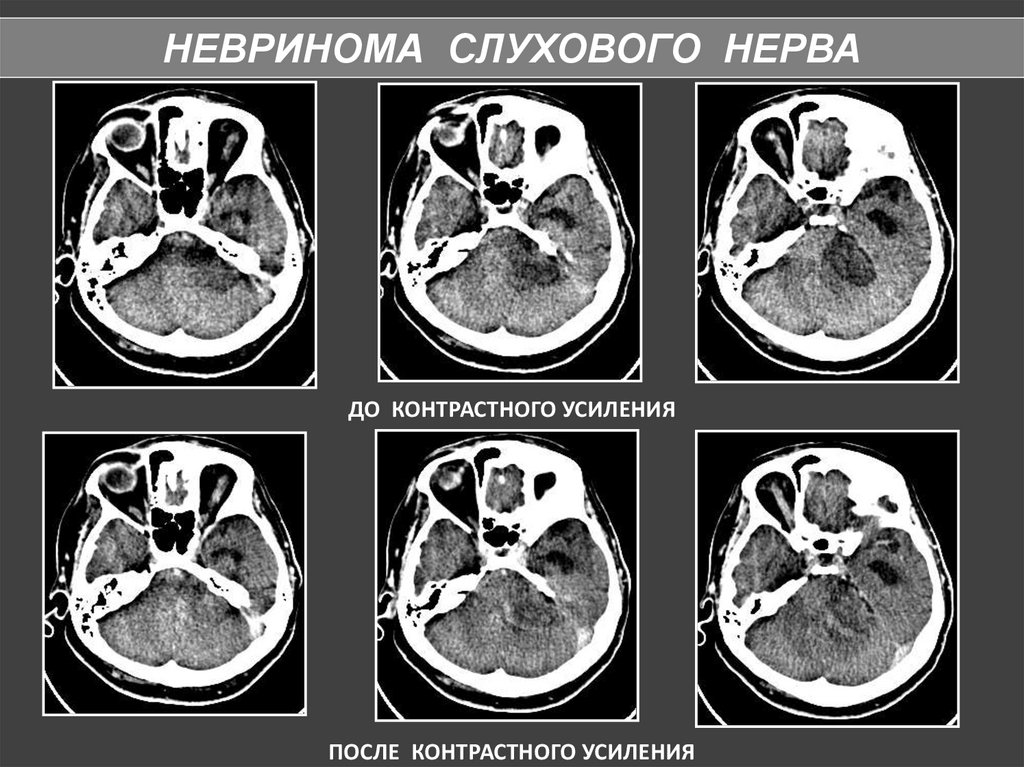

НЕВРИНОМА СЛУХОВОГО НЕРВА

По локализации выделяют 3 типа неврином:

- внутриканальные – расположены в пределах

внутреннего слухового прохода;

- внутри- и внеканальные – расположены, как

во внутреннем слуховом проходе, так и в

мостомозжечковой цистерне;

- внеканальные невриномы исходят из той

части

нерва,

которая

располагается

в

мостомозжечковой цистерне.

80.

КТ — признаками опухоли слухового нерва являются:

расширение слухового прохода, наличие округлого, реже

овального объемного образования, зачастую с очагами

кистозной дегенерации и хорошей реакцией на усиление,

острый угол между поверхностью опухоли и задней

поверхностью височной кости

ВСП шире 8 мм,

асимметрия >2 мм

подозрительны

ДО КОНТРАСТНОГО УСИЛЕНИЯ

ПОСЛЕ КОНТРАСТНОГО УСИЛЕНИЯ